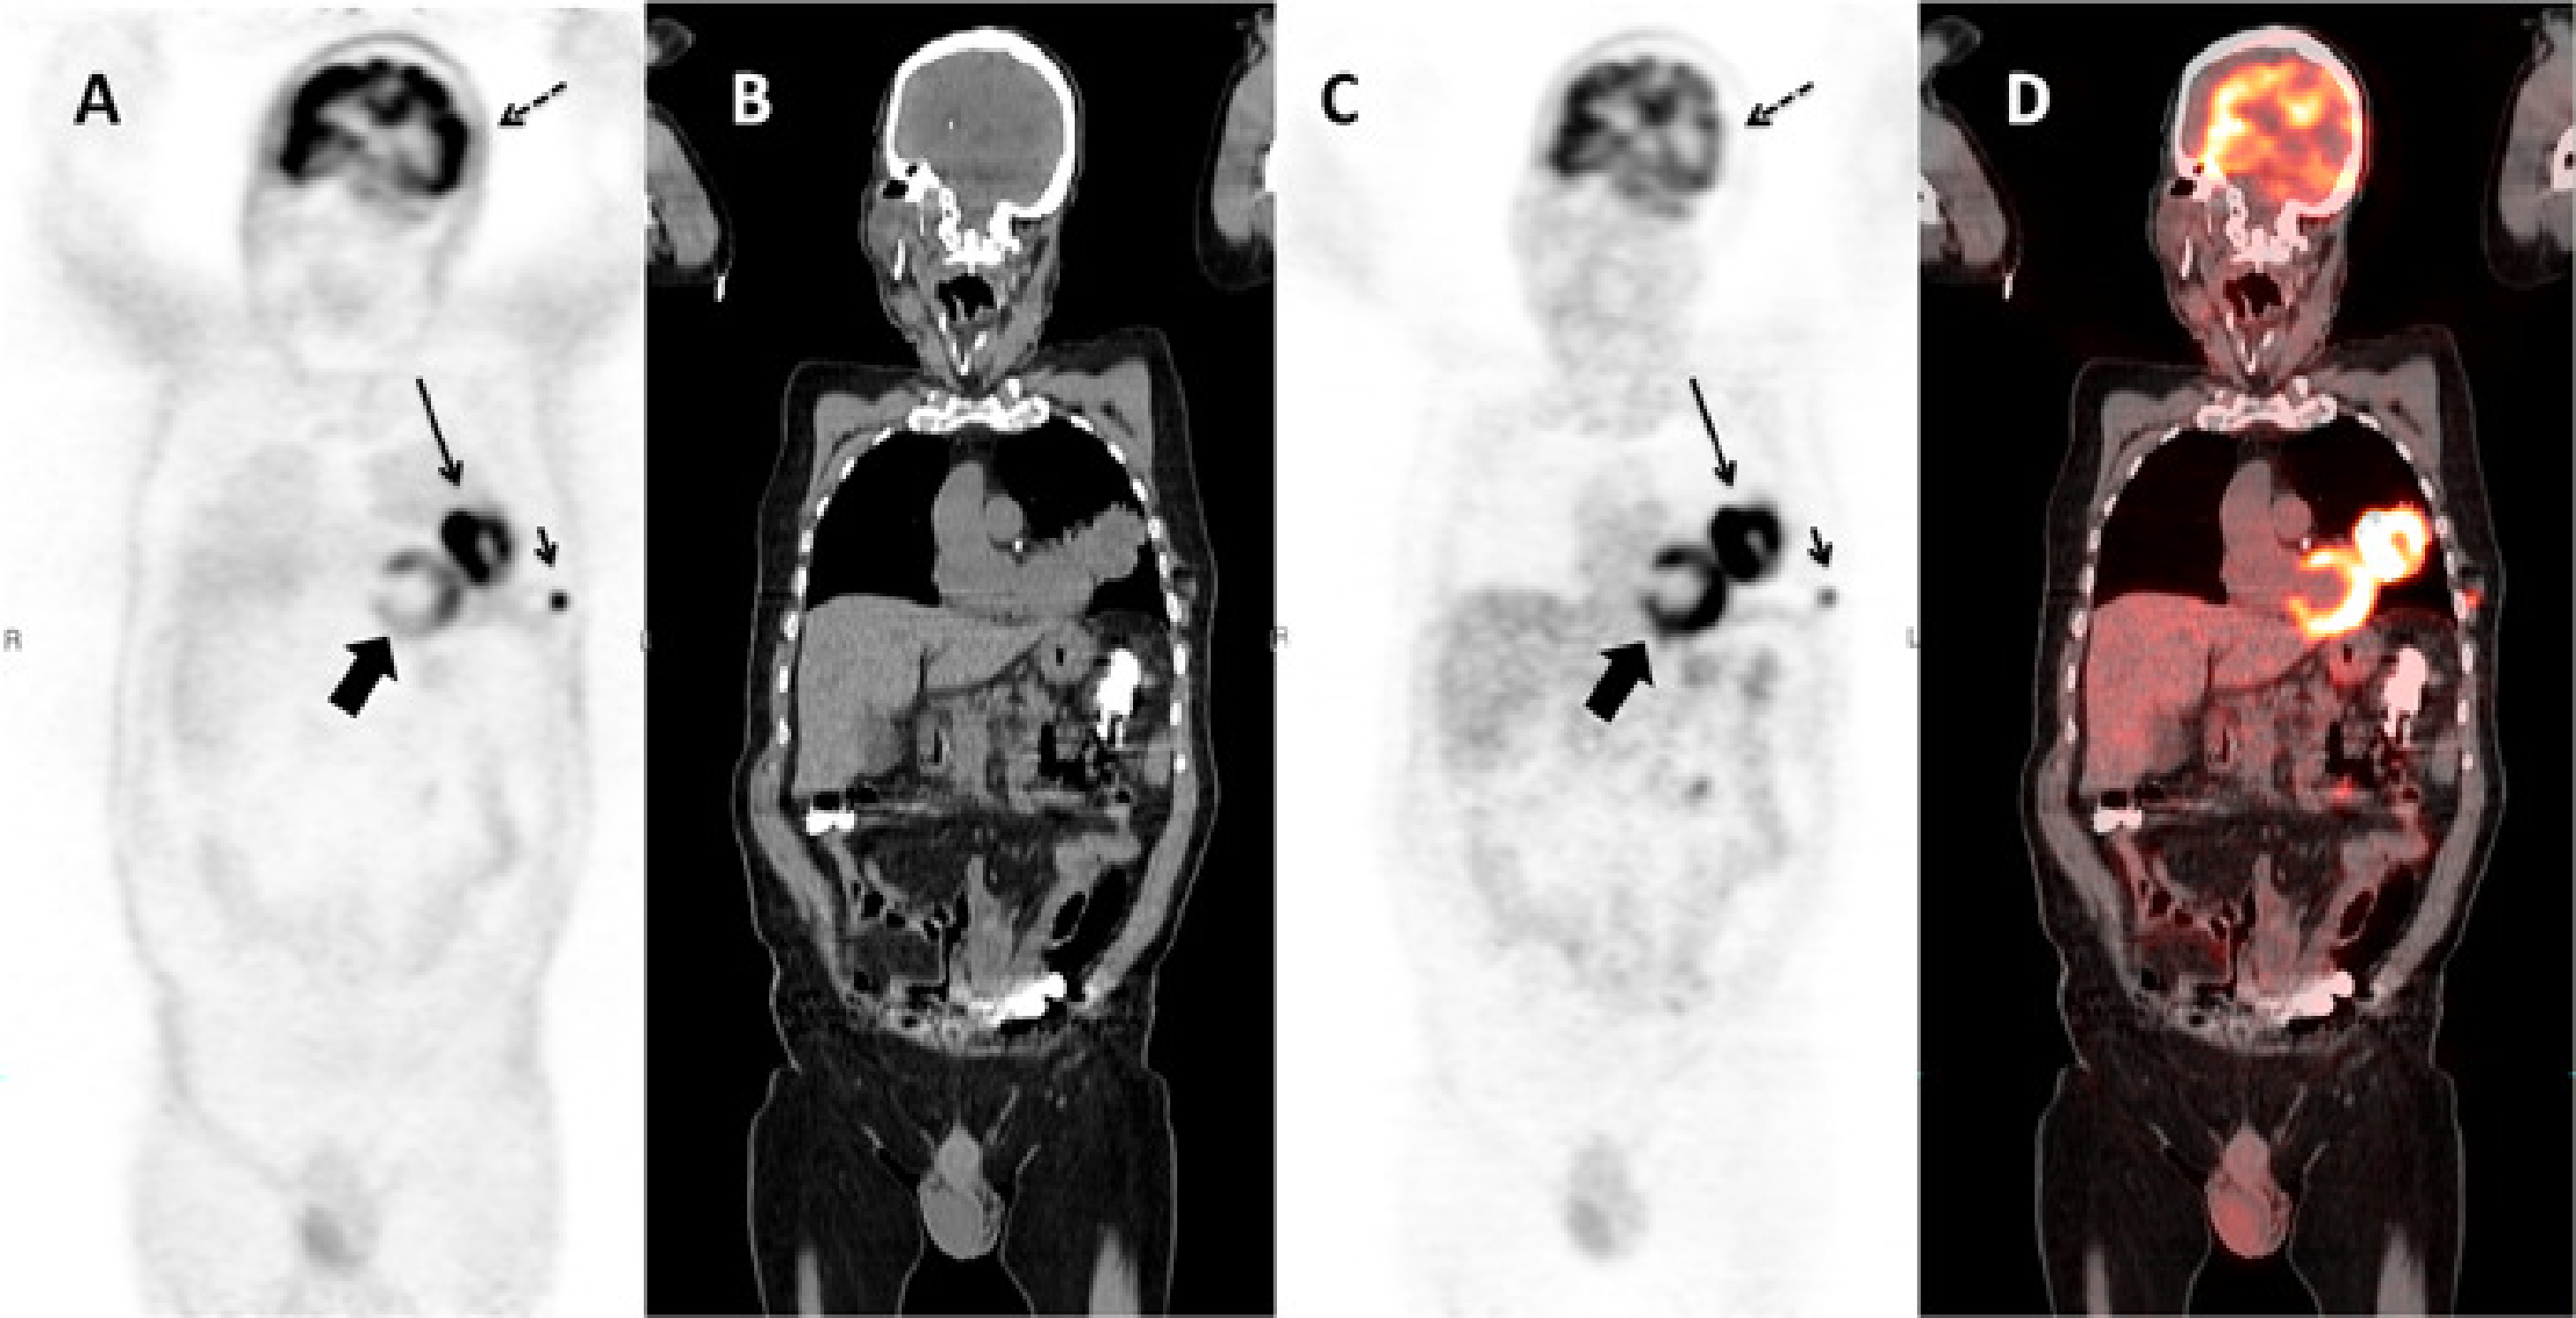

Another example is given in Figure 13. Because of potential attenuation correction artifacts, it is good practice to always make a reconstruction of the PET image without attenuation correction (Figure 13.A). This image has of course always many artifacts too, but these artifacts tend to be similar in all patients, so one can learn to read such images. Comparison of the image with and without attenuation correction may reveal subtle attenuation correction artifacts, which otherwise might lead to the wrong diagnosis. Such an artifact is present in the brain in Figure 13.C, which shows a left-right asymmetry caused by a motion artifact.

Figure 13:Coronal slice of a whole body PET/CT study reconstructed without (A) and with (C) attenuation correction based on a whole body CT (B). PET and CT are combined in a fusion image (D). The relative intensity of the subcutaneous metastasis (small arrow) compared to the primary tumor (large arrow) is much higher in the non corrected image than in the corrected one, because the activity in this peripheral lesion is much less attenuated than the activity in the primary tumor. A striking artifact in (A) is the apparent high uptake in the skin and the lungs. Note also that regions of homogenous uptake, such as the heart (thick arrow), are no longer homogenous, but show a gradient. The uptake in the left side of the brain (dotted arrow) is apparently lower than in the contralateral one in (C). The fusion image shows that the head did move between the acquisition of the CT and the emission data, resulting in an apparent decrease in activity in the left side of the brain due errors in the attenuation correction.